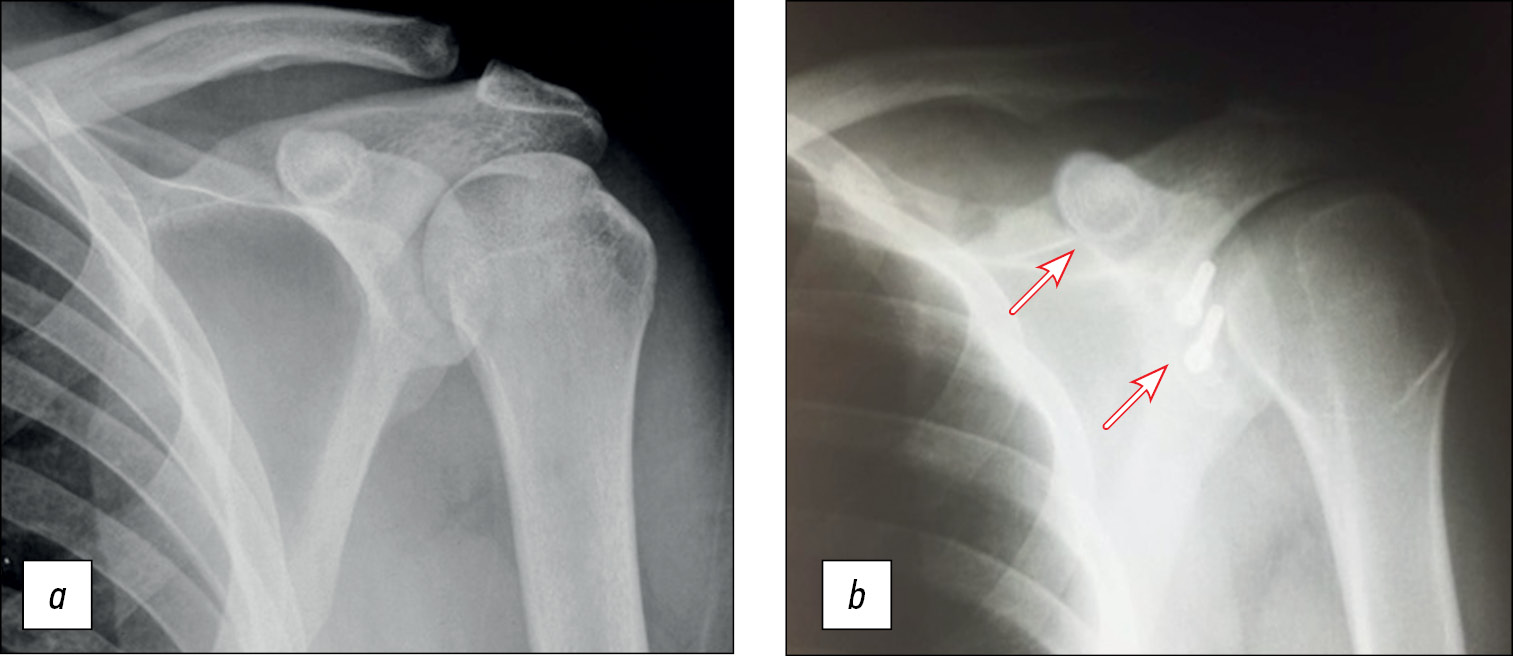

Пациент Н., 27 лет, с рецидивирующей нестабильностью левого плечевого сустава (заслуженный мастер спорта по спортивной гимнастике).

В 2022 году выполнена артроскопическая стабилизация с использованием свободного костного аутотранс-плантата правого плечевого сустава (рис. 15).

Рис. 15. Рентгенография правого плечевого сустава: а — до операции, b — через 6 месяцев после неё.

Fig. 15. X-ray of the right shoulder joint: a — before surgery, b — 6 months after it.

Положение костного аутотрансплантата через 6 мес после операции. Тестирование функционального состояния мышц через 6 месяцев после операции для оценки спектральной мощности на левой руке (рис. 16–18).